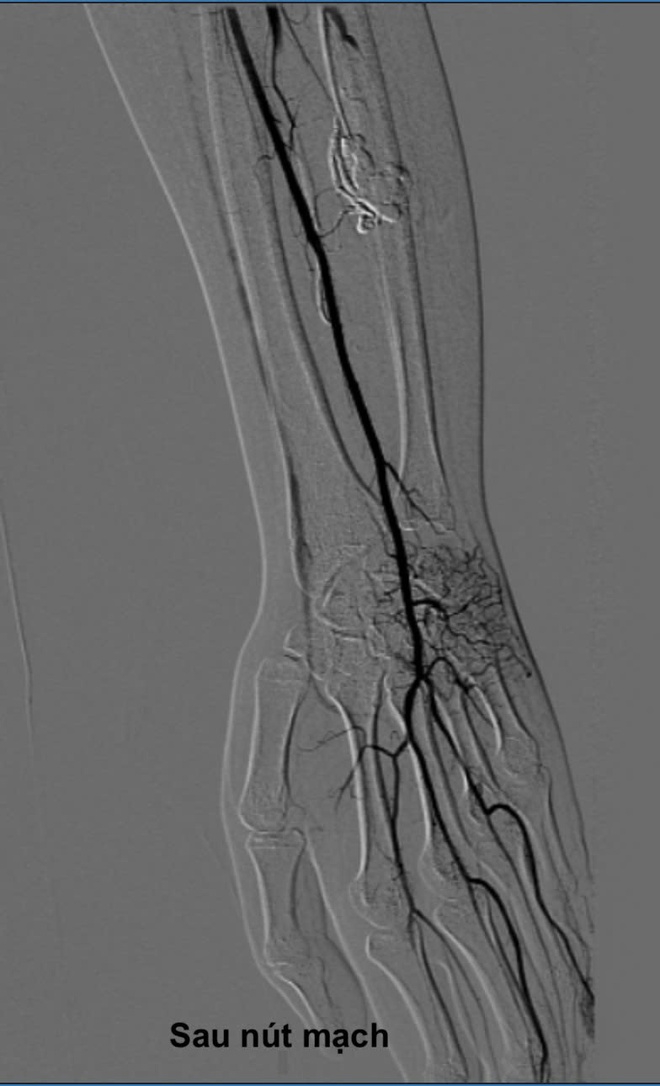

Sau khi hội chẩn kỹ lưỡng, các bác sĩ quyết định không phẫu thuật mở truyền thống mà chỉ định cho bệnh nhân L.Q. thực hiện phương pháp can thiệp nút mạch qua da – một kỹ thuật điện quang can thiệp hiện đại, ít xâm lấn.

Dưới sự hướng dẫn của máy chụp mạch kỹ thuật số (DSA), bác sĩ sử dụng một cây kim rất nhỏ chọc trực tiếp qua da, đi chính xác vào ổ dị dạng nằm sâu trong cơ cẳng tay. Sau đó, cồn tuyệt đối (absolute ethanol) được bơm vào qua kim để làm xơ hóa và bịt kín hoàn toàn các mạch máu bất thường.

Toàn bộ quá trình can thiệp chỉ diễn ra trong khoảng một giờ. Bệnh nhân hoàn toàn tỉnh táo và không phải trải qua một cuộc phẫu thuật mở nào.

Ngay sau can thiệp, ổ dị dạng đã được bịt kín, dòng máu được tái lập bình thường. Chỉ sau vài ngày, các triệu chứng đau tê ngón tay của bệnh nhân Q. đã giảm rõ rệt.